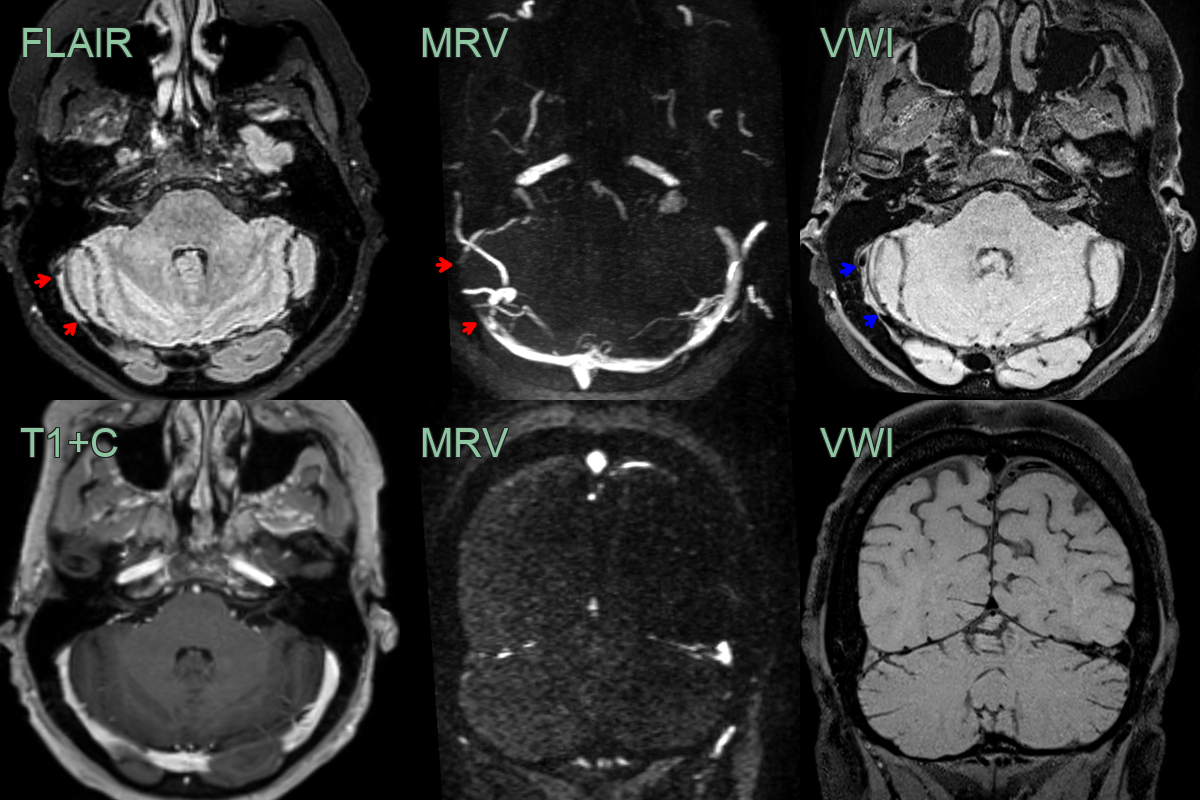

- A 35-year-old patient presented 3 months after the onset of a headache.

- FLAIR showed a hyperintense segment in the right transverse sinus with absent flow on the MRV (red arrows).

- While thrombus was strongly suspected, this was confirmed with black blood imaging (blue arrows), removing the possibility of the findings on FLAIR and MRV were artefactual.

- Notice that on the post-gadolinium images, the filling defect is not apparent due to thrombus enhancement.